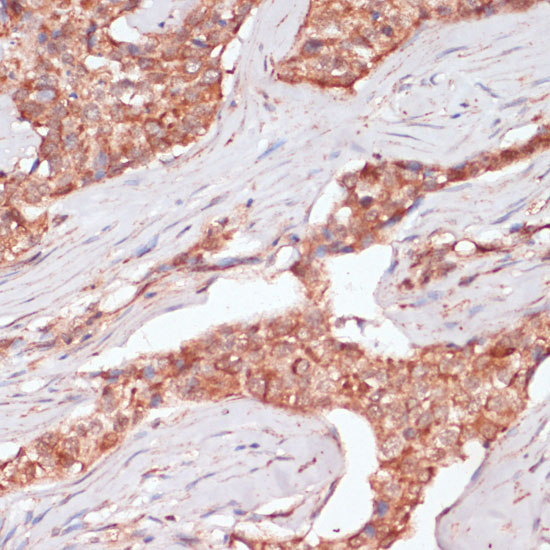

Immunohistochemistry of paraffin-embedded human colon carcinoma using ACAT2 at dilution of 1:100 (40x lens).

Immunohistochemistry of paraffin-embedded human oophoroma using ACAT2 at dilution of 1:100 (40x lens).

Immunohistochemistry of paraffin-embedded human breast cancer using ACAT2 at dilution of 1:100 (40x lens).